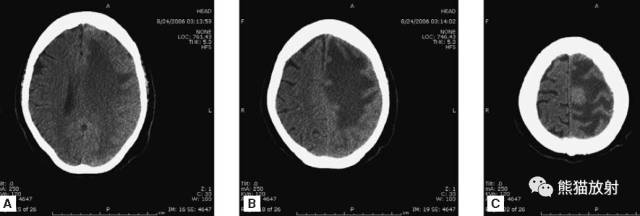

7、脑积水

脑积水,并脑室分流。

8、占位性病变

急诊患者的症状大多由于病变的占位效应所引起。能引起脑水肿及占位效应的病变有:原发肿瘤或转移瘤,血管畸形,炎性病变(弓形虫、脑脓肿)。

本例:肿瘤密度较高,邻近大脑镰,周围可见大片低密度水肿区。